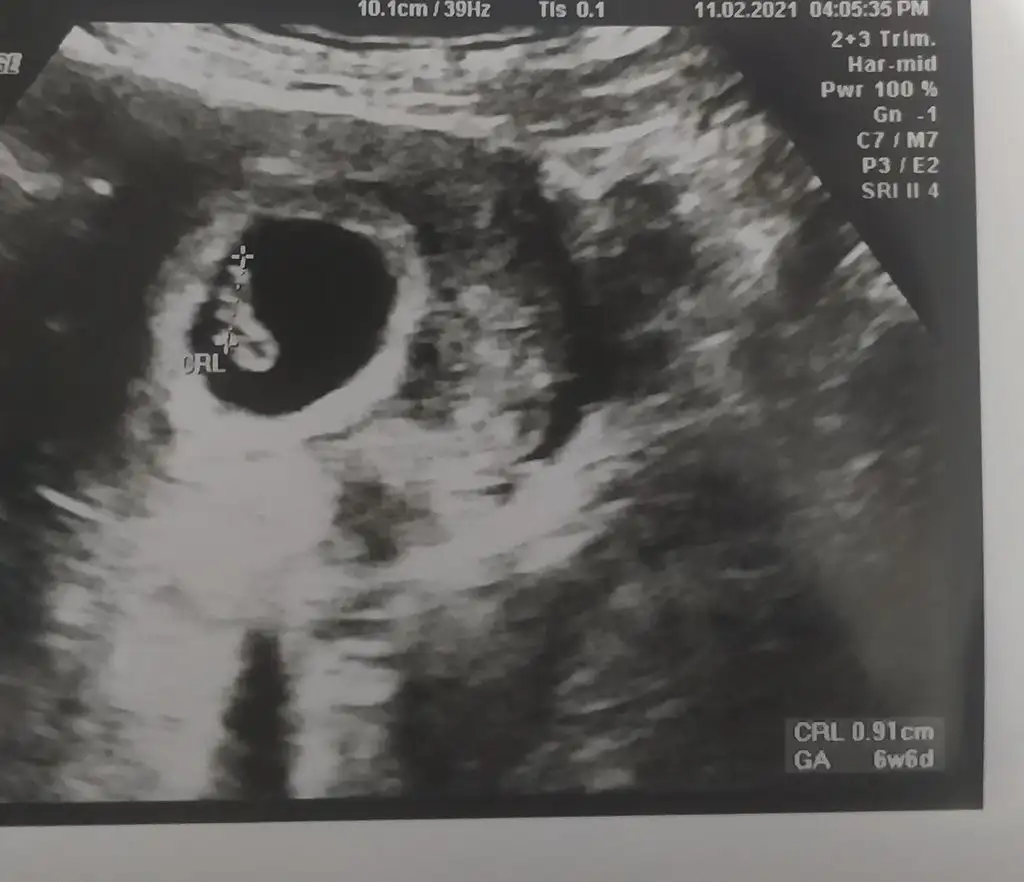

6+6 haftalık karından ultrason bana da yorum yapabilir misiniz?

Eklentiler

• 20210211_234714.webp

25,1 KB · Görüntüleme: 121